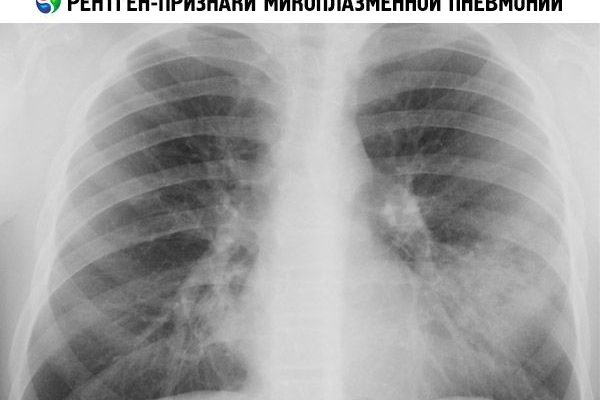

Myoplastic пневмония проявляется в радиологических фотографиях следующим образом:

- Легочная паттерн становится толще и толще;

- В половине пациентов есть интерстициальное воспаление, то есть стенки, разделяющие легочные пузырьки, которые сделаны из рыхлой соединительной ткани;

- В редких случаях есть стимул легочной ткани в небольших участков или сегментов, характеризуется неоднородностью и не имеют четких границ из редко двусторонняя;

- В очень редких случаях, есть коренной настой.

В большинстве случаев микоплазма пневмонии могут быть обнаружены с помощью РТГ и МРТ. Иногда, однако, эти диагностические методы не являются достаточными. Затем серологическое анализ мокроты и мазков, взятых из полости рта проводят.